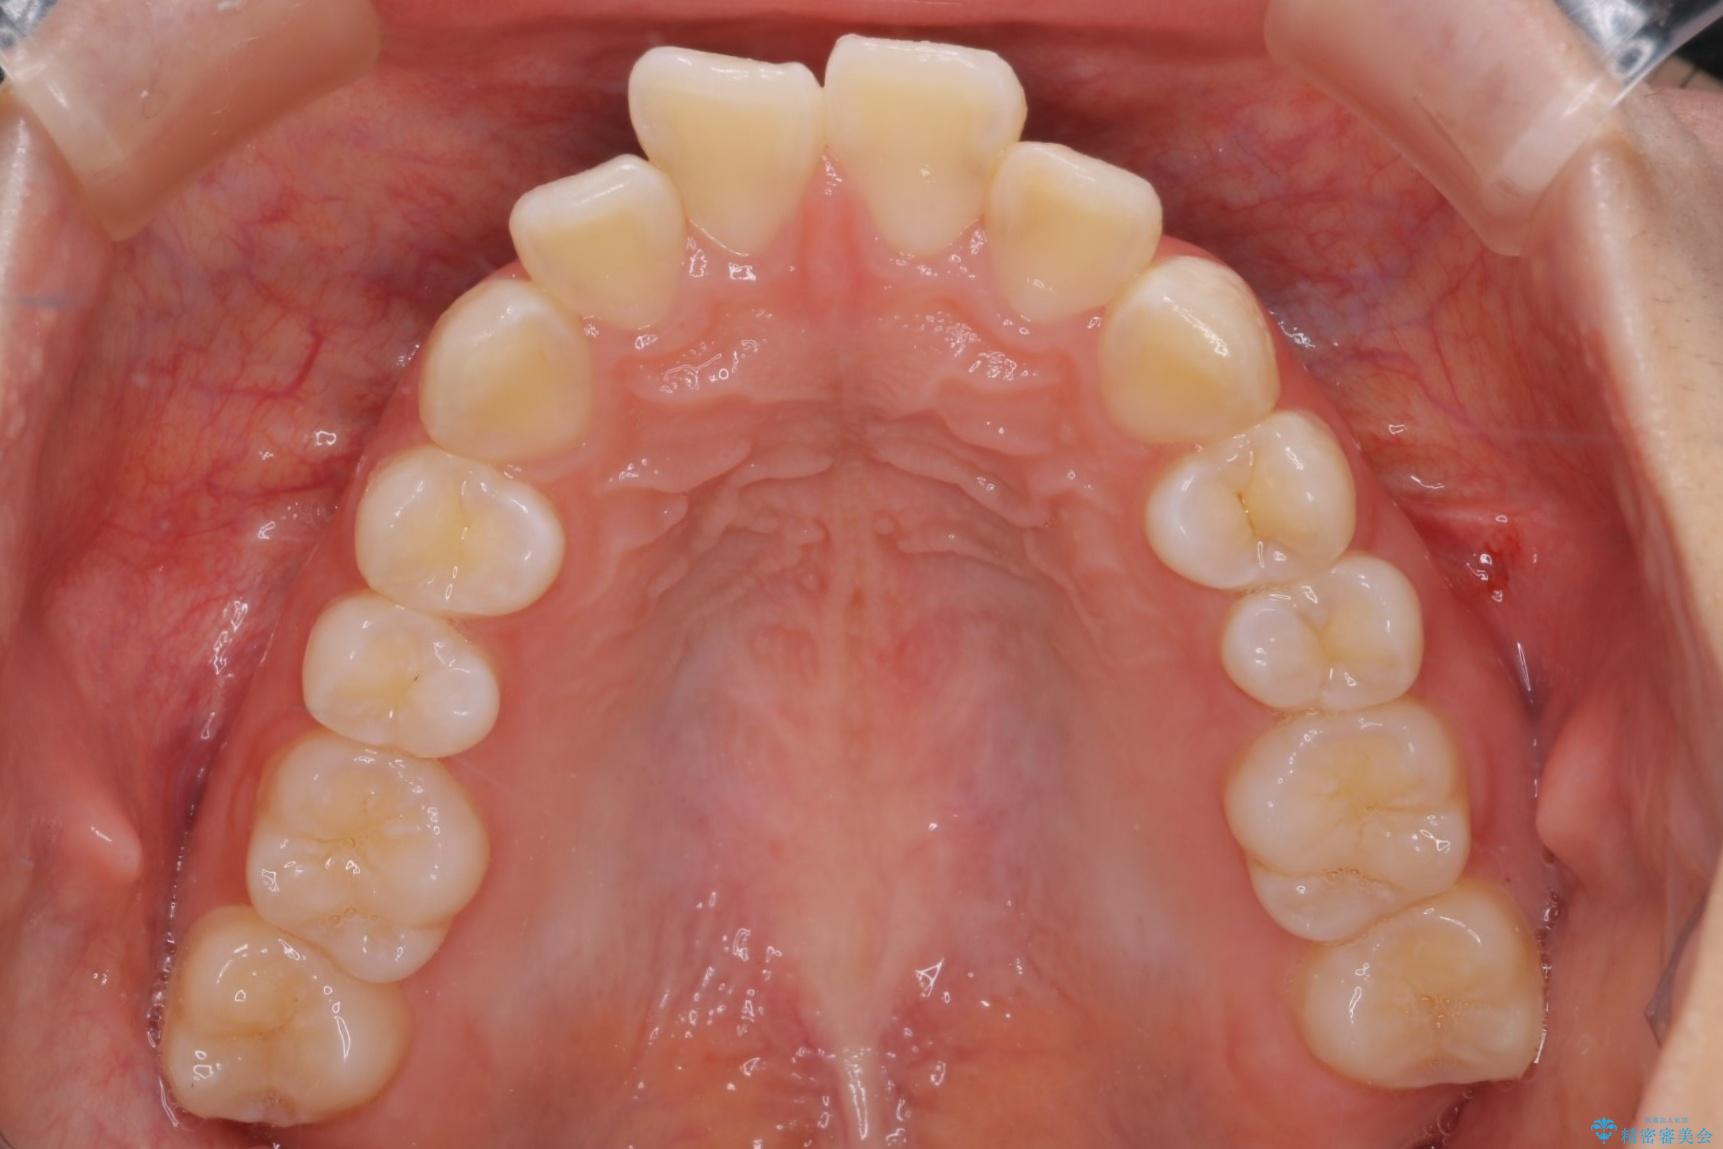

前歯のガつきと口元が出ていることを気にされご来院された患者様です。

治療計画

上下4番目の歯を抜歯してガタつきを改善しながら口元を下げる治療計画を立てました。